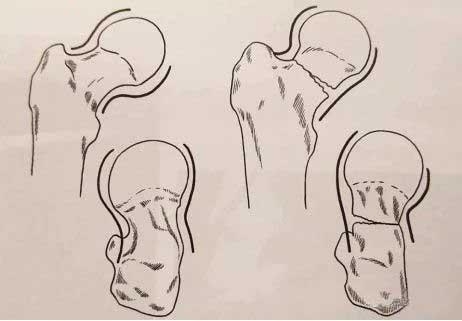

Clasificación de fracturas de Delbet

Las fracturas de tipo I son relativamente raras, son fracturas transepifisarias y fracturas epifisarias SH I. Según si hay luxación, se divide en tipos A y B, que se observan principalmente en niños pequeños. Entre ellas, las fracturas epifisarias acompañadas de luxación, 100% reportadas en la literatura, provocarán necrosis avascular de la cabeza femoral y cierre prematuro de la epífisis.

Las fracturas de tipo Ⅱ son el tipo más común de fracturas de cuello femoral en niños. Son fracturas transcuestres. La mayoría de ellas son desplazadas, lo que puede causar fácilmente una necrosis avascular de la cabeza femoral. La necrosis está relacionada con el grado de desplazamiento.

Las fracturas de tipo Ⅲ son fracturas basales, también llamadas fracturas transcervical-trocánter, y la incidencia de necrosis de la cabeza femoral es baja.

Las fracturas de tipo IV son fracturas intertrocantéreas y la incidencia de necrosis de la cabeza femoral es menor.